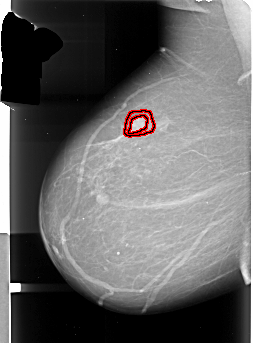

A_1004_1.LEFT_MLO

FILE: A_1004_1.LEFT_MLO.OVERLAY

TOTAL_ABNORMALITIES 1

ABNORMALITY 1

LESION_TYPE MASS SHAPE IRREGULAR MARGINS SPICULATED

ASSESSMENT 5

SUBTLETY 5

PATHOLOGY MALIGNANT

TOTAL_OUTLINES 2

BOUNDARY

CORE